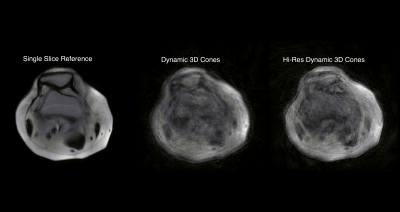

Recent work by this group, demonstrated the potential of combining multiscale low-rank reconstruction with a 3D golden-ratio reordered cones acquisition to generate real-time 4D images in the knee.Figure 1 shows the early results in this area, and while the images are blurry, patellar motion is visible1.

A single slice of a 4D data sent showing the potential of combining multi-scale low-rank reconstruction with a 3D golden-ratio reordered cones acquisition to generate real-time 4D images